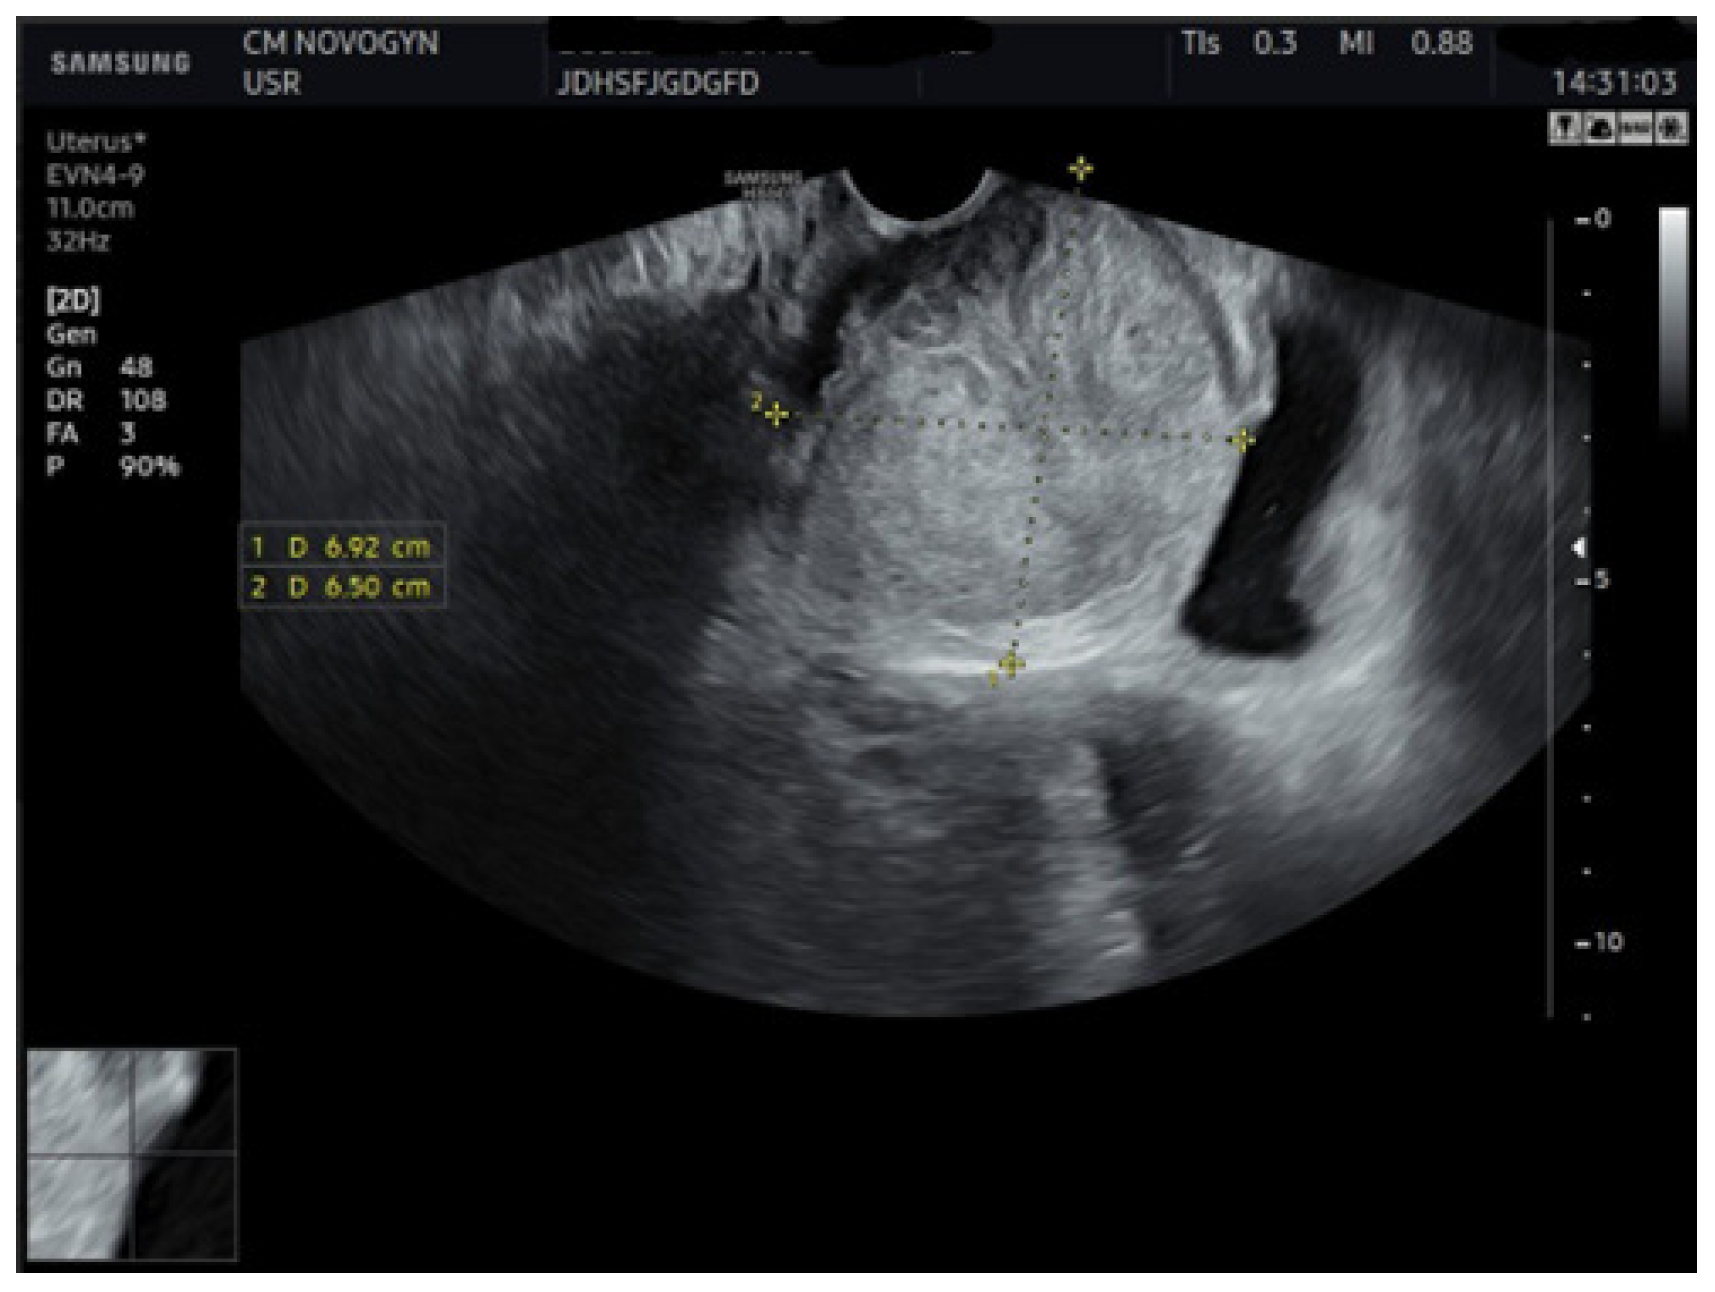

2.4. Imaging Studies

3.1. Imaging Characteristics and Diagnostic Precision